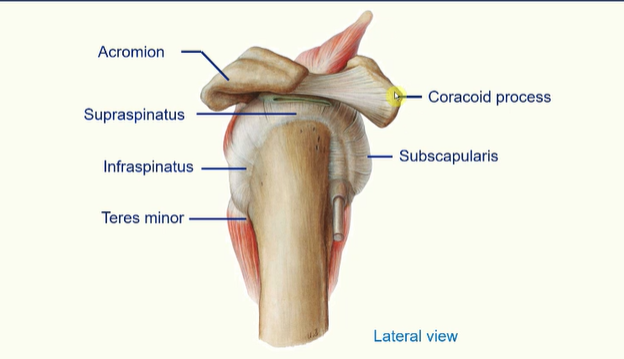

The Rotator Cuff

the rotator cuff is a group of muscles whose tendons surround the glenohumeral joint

as well as providing movement to the upper limb these muscles strengthen the joint

these muscles are;

subscapularis

supraspinatus

infraspinatus

teres minor

Rotator Cuff Muscles

supraspinatus initiates abduction of the arm

infraspinatus allows lateral rotation of the humerus

teres minor allows lateral rotation of the humerus

subscapularis allows medial rotation of the humerus